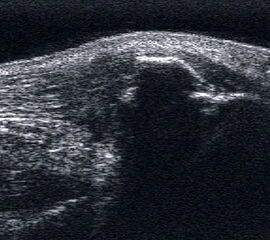

Ruptur der Tibialis anterior Sehne mit retrahiertem Stumpf und umgebendem Hämatom.

Abbildung 49

Lagerung: Rückenlage.

Schnittführung: Ventraler LS und TS über dem OSG und dem Mittelfuß.

Referenzstrukturen: Distale Tibia und Talusrolle, Kahnbein, Cuneiforme-Knochen und Metatarsalia,Sehnen der Mm. tibialis anterior, extensor digitorum longus.

Befunde: Oberhalb der Gelenkkapsel echogene longitudinale parallele Struktur der Strecksehnen. Als dickste Sehne liegt medial die Tibialis-anterior-Sehne, die selten reißt. Die Tibialis anterior Sehne ist als Extensor des Fußes für die Kinematik der Abrollbewegung bedeutsam. Halo-Phänomen und echoarme Verdickung bei zumeist akuter Tendinopathie. Nach Riss oftmals weite Retraktion nach proximal mit umgebender Flüssigkeit oder Hämatom (Abb. 49).